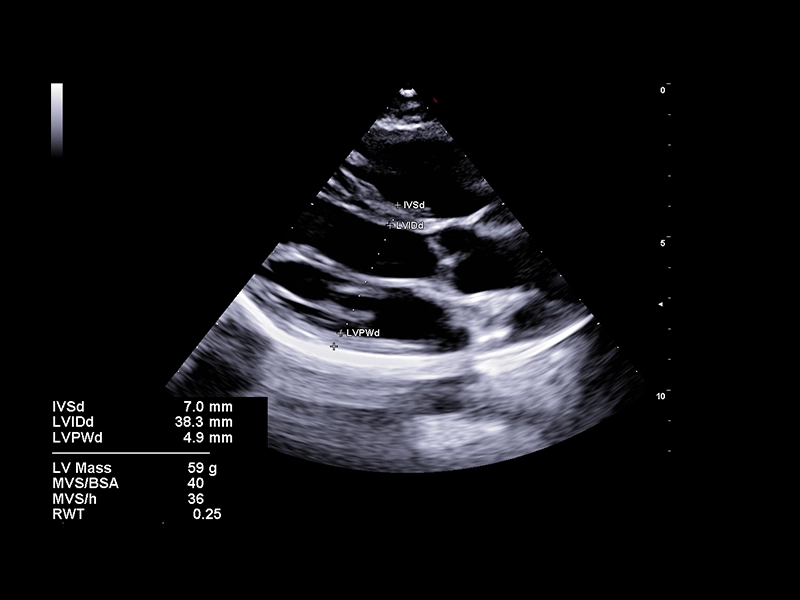

MyLab™E80 - AutoCM

MyLab™E80 - AutoCM